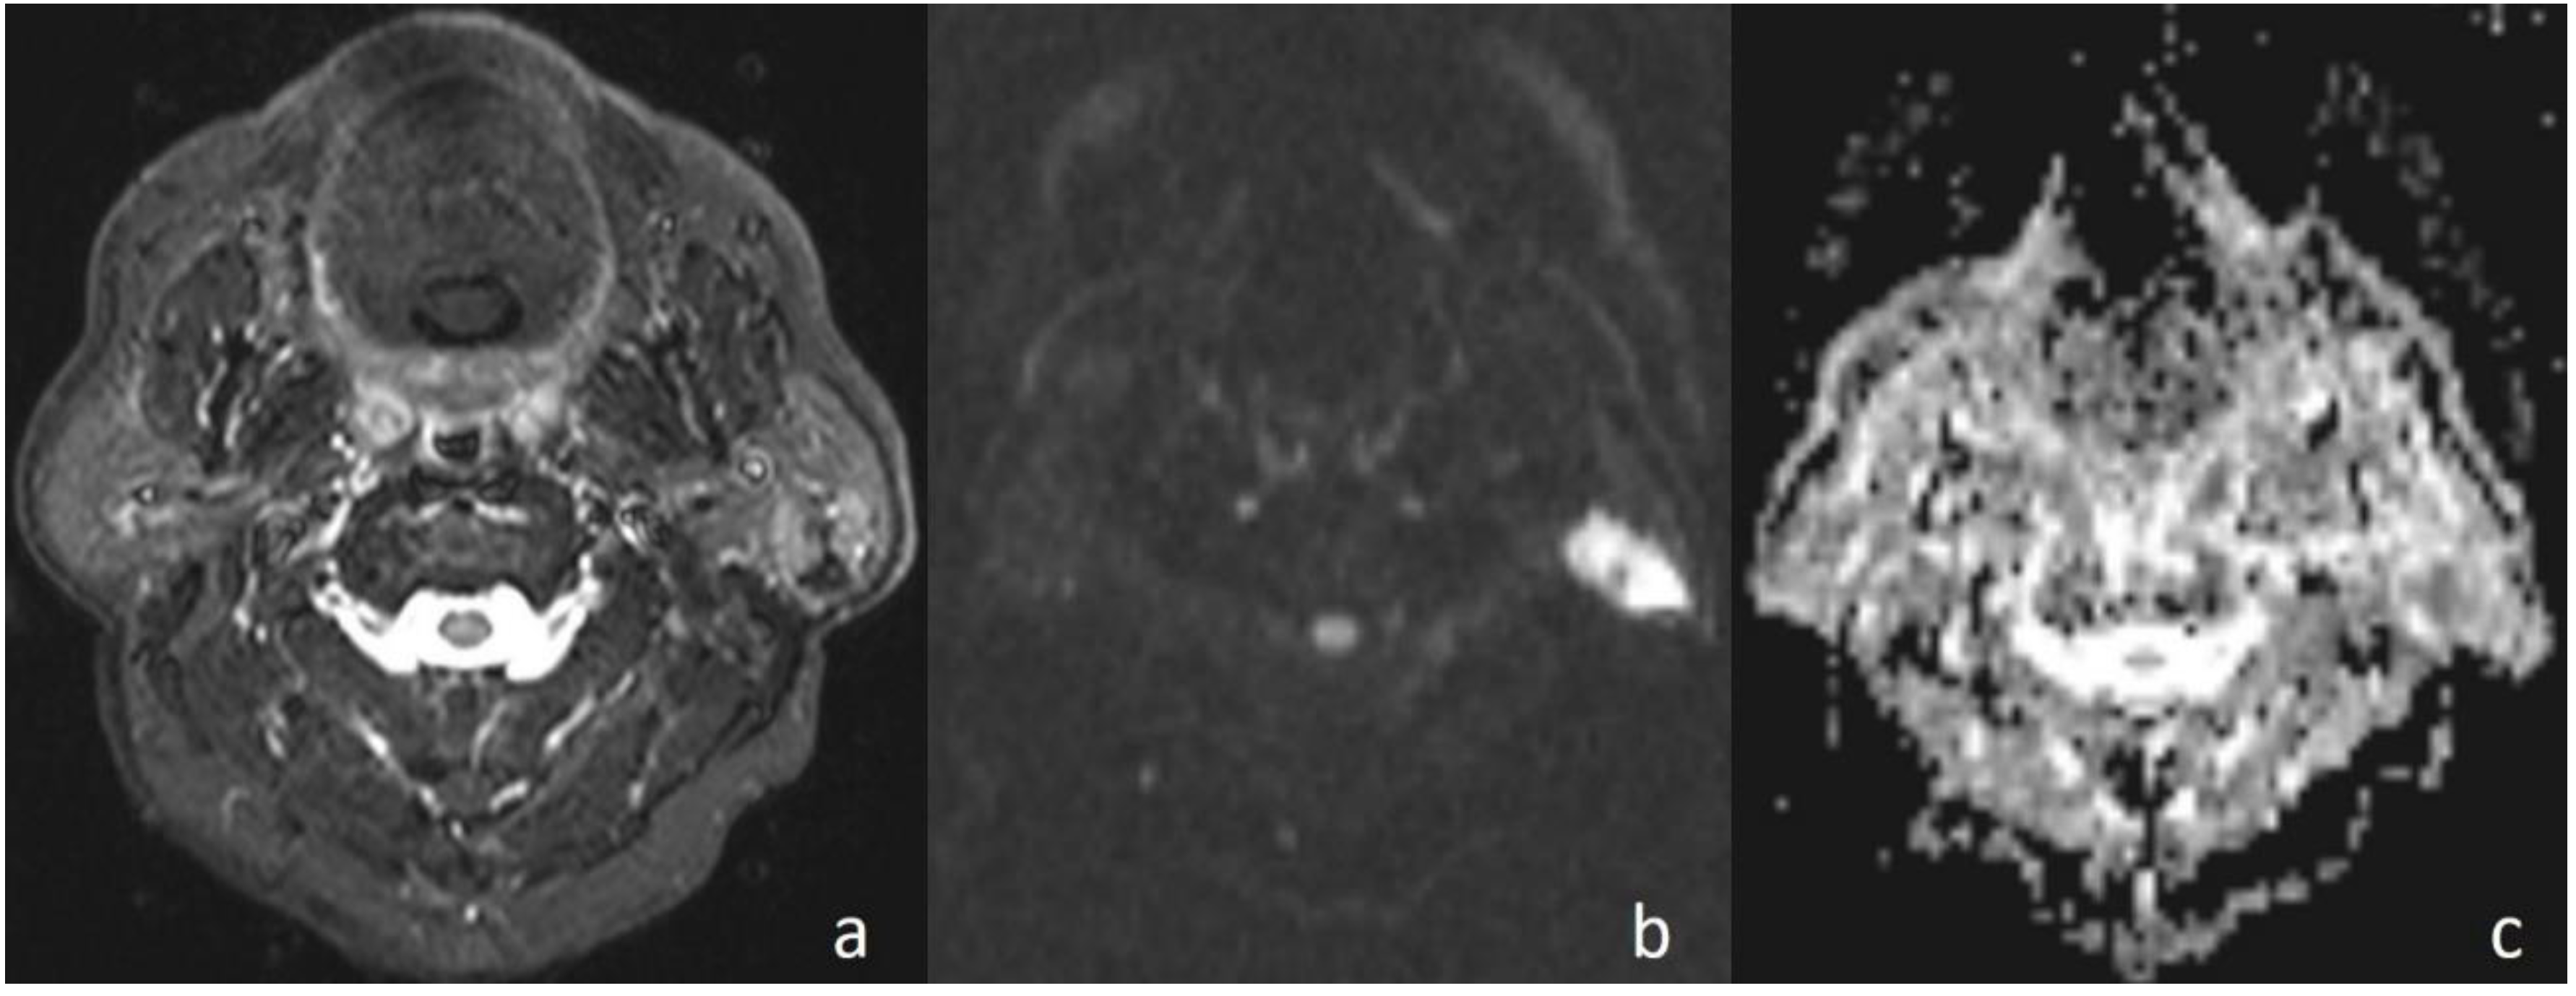

Figure 3. Undifferentiated nasopharyngeal carcinoma. (a) Axial T2WI shows bilateral metastatic cervical lymph nodes; (b) lymph node, on the left side of the neck, shows high signal intensity on DWI; and (c) the mass is hypointense on the ADC map (ADC value of 0.91 × 10−3 mm2/s).

In the current study, the mean ADC value of benign masses with high signal intensity was significantly (Figure 2) higher than that of malignant (Figure 3) masses with low signal intensity. These differences in ADC values may be explained by the differences in the histopathological characteristics of benign and malignant tumors. Generally, malignant tumors show hypercellularity and have enlarged nuclei, and hyperchromatism. These histopathological characteristics reduce the diffusion space of water protons in the extracellular and intracellular regions [13,14].